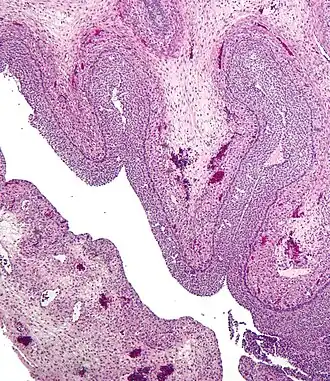

Pathology

• Corpus luteum cyst: hemorrhage into persistent corpus luteum. Commonly regresses spontaneously.